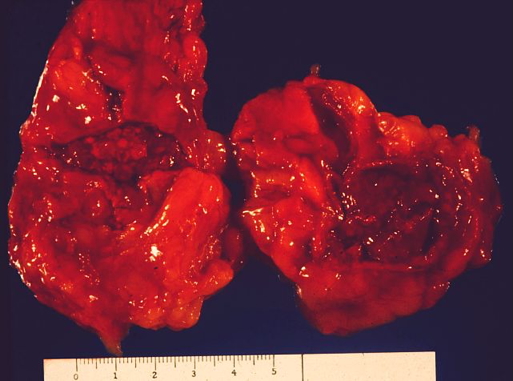

Macroscopic

- Adrenal glands replaced by large haemorrhagic masses

- Fresh blood clots obscure normal gland structure